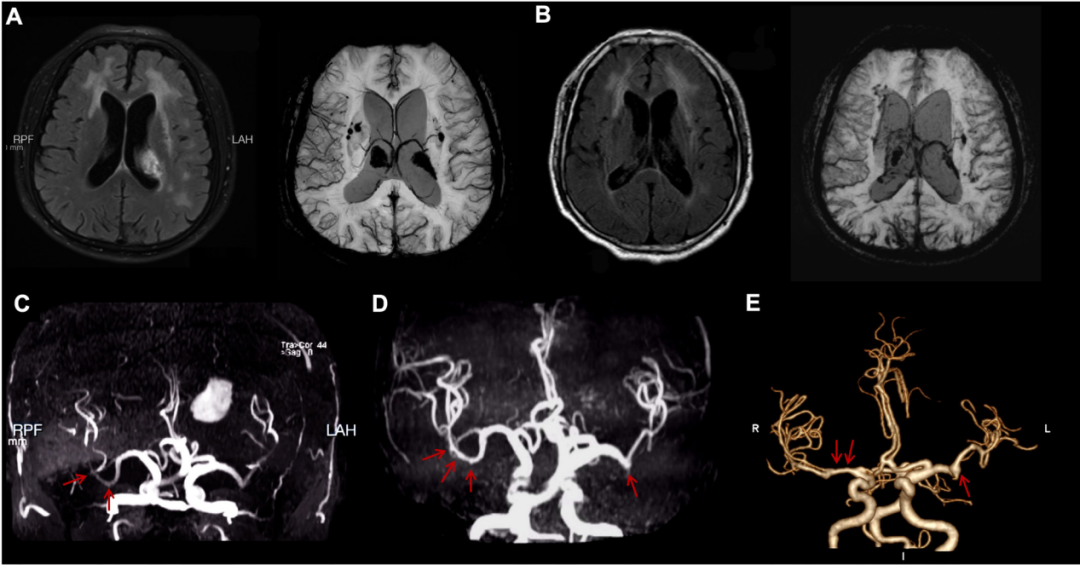

与此同时,该团队在2026年1月份《Stroke》(中科院一区,IF = 8.9)杂志上报道了一例罕见的神经布鲁氏菌病相关脑血管病变。该研究通过动态影像学证据,首次完整展示了由布鲁氏菌感染引发的脑白质损害、脑出血及大脑中动脉串珠样扩张,经过抗感染治疗后呈现出动态改变。

这一发现为感染相关脑血管病提供了全新的影像学表型,拓展了神经布鲁氏菌病的临床认知。齐鲁医院神经内科副研究员段若楠、医师高天宇为共同第一作者,赵玉英为通讯作者。